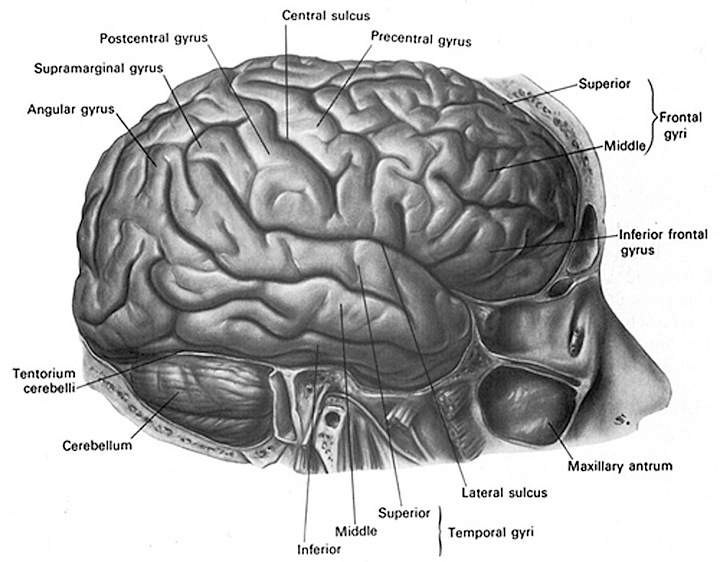

Супрамаргинальная извилина: Функции и Исследования